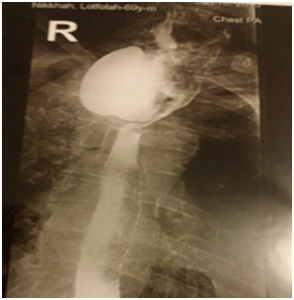

All six patients were symptomatic Four of patients were male. Age of patients was 65 to 80years. Four of patients came with dysphasia aspiration, halitosis, and malnutrition and regurgitation, one of this patient present three period with aspiration pneumonia and hospital admission. One of patients underwent endoscopic diverticulotomy and 24 hour after this procedure present with odynophagia, fever and neck subcutaneous emphysema With B-swallow perforation of diverticula was demonstrated, this patient underwent neck exploration and diverticulectomy and drainage. Diagnostic tools of five cases was B-swallow and esophagoscopy (Figures 1-5). One came with food marital retention and pain and neck mass tender mass. One patients referred with erithem, redness and criptation of neck with diagnosis of diverticulitis (Figures 6 & 7). Two cases underwent flexible endoscopic diverticulotomy, one failed and another ones complicated with perforation. The most common surgical approaches was diverticulectomy and myotomy in four patients (Figures 8 & 9). Food debris was present in one patient (Figure 10). Two of patients underwent diverticulectomy without myotomy. Complication and mortalities were zero. In two years flow-up, Outcome was good.

Figure 1 Show swallow of a 75 year old man with huge Zenker's diverticulum.

Figure 2 Show swallow of a 85 year old woman with huge Zenker's diverticulum.

Figure 3 Show swallow of a 65 year old man with huge Zenker's diverticulum.

Figure 4 Show swallow of a 80 year old man with huge Zenker's diverticulum.

Figure 5 Show swallow of a 78 year old man with huge Zenker's diverticulum.